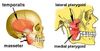

Which 3 pairs of muscles are responsible for closing the jaw?

Masseter, Temporalis and Medial pterygiod

Which pair of muscles is responsible for opening the jaw?

Lateral pterygoid

What is the origin and insertion of the masseter m.?

Angle of mandible to zygomatic arch

What is the origin and insertion of the temporalis m.?

Coronoid process of mandible to temporal fossa

What is the origin and insertion of the medial pterygoid m.?

Angle of mandible (medial side) to pterygoid plates of sphenoid bone

What is the origin and insertion of the lateral pterygoid m.?

Condyle of mandible to pterygoid plates of sphenoid bone

Which nerve supplies all of the muscles acting on the jaw?

Mandibular division of trigeminal nerve – CN V3